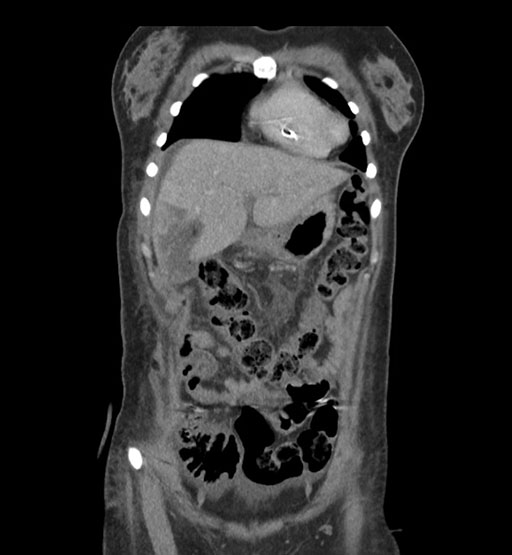

Coronal Arterial